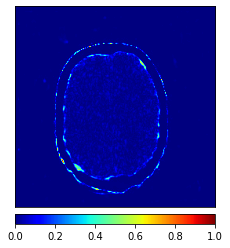

Tables 1 and 2 show the quantitative accuracies of various methods in generating CT and MR images, respectively. As can be seen, DC-cycleGAN outperforms other methods in terms of MAE, PNSR and SSIM. This is mainly due to the dual contrast loss that is integrated into the DC-cycleGAN structure.

Moreover, Figs. 6 and 7 show the synthesized MR and CT images along with the errors between the real and synthesized images by different methods, respectively. It can be seen that the synthesized images by DC-cycleGAN are more identical to the real ones as compared with other methods. This indicates that effectiveness of SSIM and CE along with dual contrast in synthesizing images. In addition, the error between the groundtruth and synthesized MR/CT images by DC-cycleGAN is relatively less as compared with other methods.